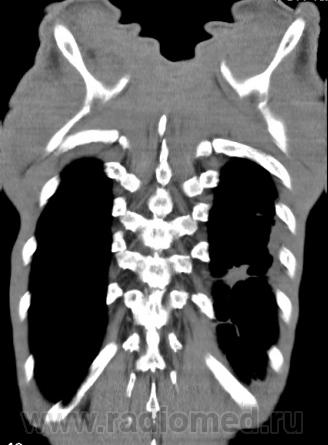

КТ - ОГК.  Ваше мнение коллеги?

На фоне консолидации полость без содержимого. Может быть всё что угодно, что сопровождается деструкцией. Нужны ещё томограммы в лёгочном окне.

Изображения выставлены все. Ваше мнение уважаемые коллеги?

Туберкулёз.

Туберкулёз?